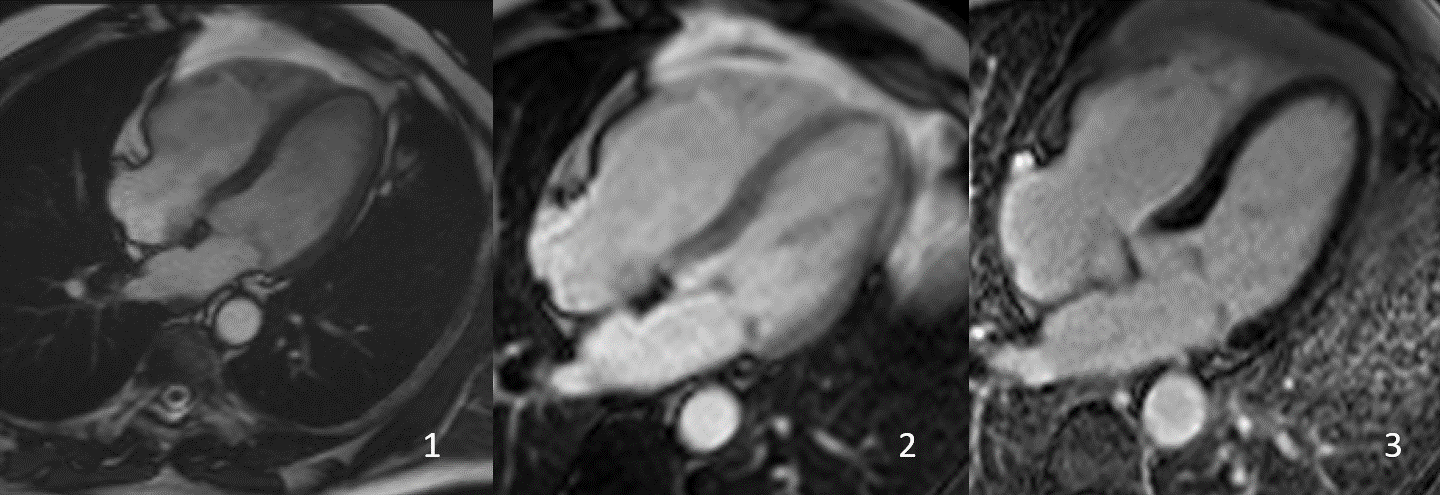

FIG 2- Localizer b-SSFP (1) and short Axis b-SSFP demonstrating the region of the artefact.